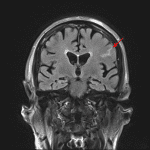

- FLAIR signal hyperintensity in the left inferior frontal sulcus

- Subarachnoid hemorrhage

Small volume acute subarachnoid hemorrhage in the left inferior frontal sulcus. No parenchymal hemorrhage, hydrocephalus, or intracranial mass effect.